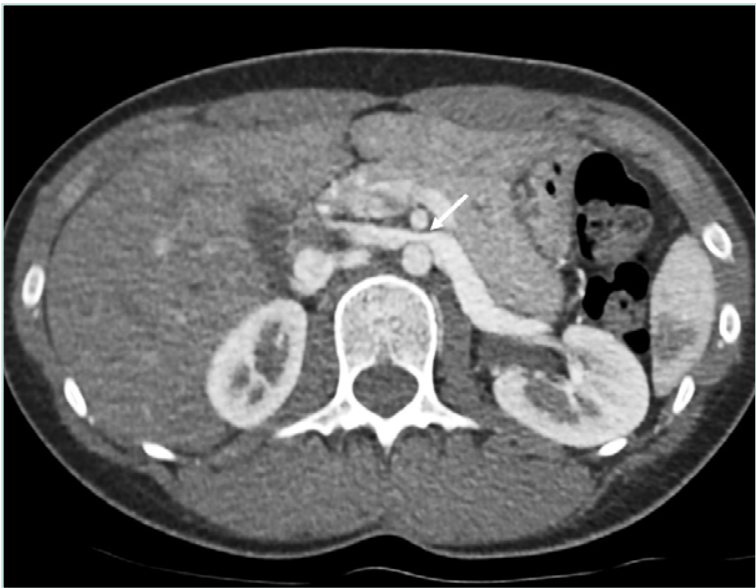

CTA provides high-resolution images of renal vasculature and adjacent structures without being invasive,21 though it lacks flow data. Sensitivity and specificity are 92% and 89%, respectively.22 CTA identifies LRV compression by comparing the diameter at the renal hilum and narrowed segment, and by evaluating the SMA– aorta angle. Normally 45° to 90°, an angle ≤35° suggests NCS.23 On axial images, the “beak” sign—an abrupt narrowing of the LRV— has a sensitivity of 92% and specificity of 89% (Figure 1). 23 Since absolute diameters vary, the hilar-to-compressed diameter ratio is more reliable, with sensitivity of 67% and specificity of 100%.23,24

Figure 1. Axial CTA image shows compressed left renal vein between aorta and SMA and characteristic “beak” sign with abrupt narrowing of the LRV at the SMA level (white arrow). CTA, computed tomography angiography; LRV, left renal vein; SMA, superior mesenteric artery.